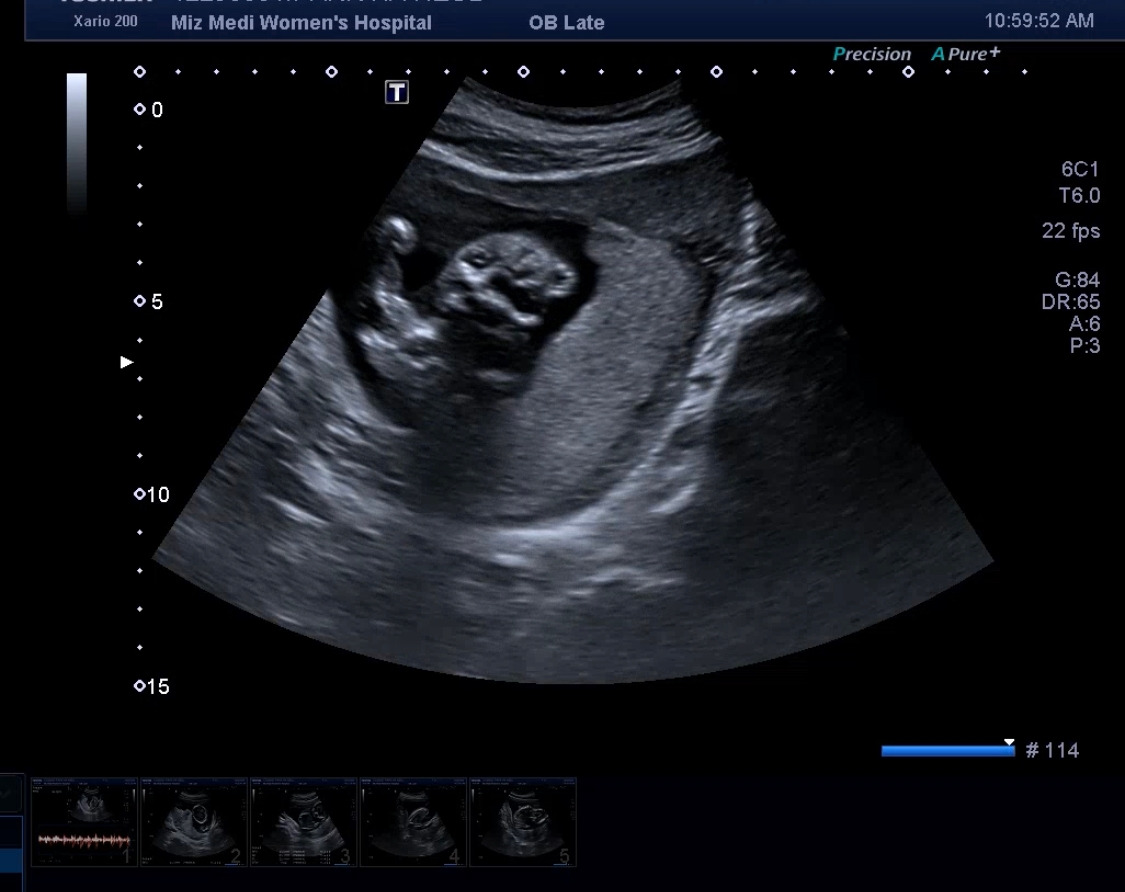

2차 기형아 검사, 그리고 성별 확인

16주 차면 거의 성별을 알게 되는 거 같아서, 사실 조금 기대를 했었다. 하지만 엄마의 변비 + 가스참으로 초음파가 제대로 보이지 않았고 의사 선생님은 딸 같다고 말을 해주고 다음번에 다시 한번 확인하자고 하셨다.

이전까지는 질초음파를 통해 아가를 봤었는데, 이제 배 초음파를 통해서 아가를 본다.

아가가 그만큼이나 컸다는 사실이 또 신기했다. 이 작은 생명체가 이렇게 하루하루 쑥쑥 내 배속에서 크고 있구나. 엄마는 너를 열심히 품고 있어야겠구나.

그렇게 의사 선생님께서는 머리, 다리, 팔, 배, 등 하나하나 봐주시면서 사이즈를 재주 시기 시작했다.

이제 아가가 커서 한 컷에 전체 모습을 담기가 어렵더라.

마지막에 마주한 우리 다올이 얼굴.....

이거 보고 엄청 웃었다. 아직 너무나 사람 같지 않아서...ㅋㅋㅋ 다올아 미안해.

엄마는 사실 널 보고 조금 무서웠어, 웃기기도 하고..

그래도 엄마는 널 사랑한단다. (그저 감정표현에 솔직한 엄마라는 것만 알아줘..)

16주차 얼굴.jpg

의사 선생님께서 영상을 보여주시는데 우리 다올이가 정말 세상 불편하게 몸을 굽히고 있더라 그래서 이곳저곳 보고 얼굴 보는 게 조금 힘들고 그랬다. 그러다가 선생님이 조금 눌러서 그런가? 불편한 자세에서 다리를 슈욱~ 피더라. 이런 모션 하나하나가 얼마나 귀엽던지..

그리고 다리는 왜 이렇게 길어 보이는지.. 내 새끼라 그런 거겠지.